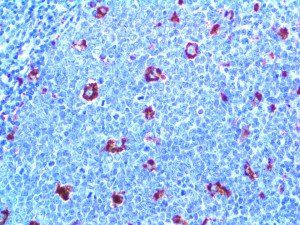

It is the ICU physician who is most likely to witness one of the deadliest manifestations of the abnormal immunological response, the cytokine storm syndrome (CSS). This response is also referred to by some as the cytokine release syndrome (CRS). CSS is characterized by continuous activation and expansion of macrophage and lymphocyte populations, which secrete large amounts of cytokines, causing the cytokine storm. This massive cytokine release is akin to hemophagocytic lymphohistiocytosis (HLH) disease, a syndrome characterized by initial unchecked and persistent activation of cytotoxic T lymphocytes and NK cells.

Clinical and laboratory manifestations of HLH include fever, enlarged liver and/or spleen, neurologic dysfunction, coagulopathy, liver dysfunction, cytopenias (i.e., low levels of erythrocytes, leukocytes, and/or platelets), hypertriglyceridemia, hyperferritinemia, hemophagocytosis, and eventually diminished NK cell activity as the immune system becomes progressively paralyzed. HLH can be familial (primary HLH) or secondary to another disease process (sHLH), such as rheumatic disease, in which it is referred to as macrophage activation syndrome (MAS, characterized by elevated ferritin).